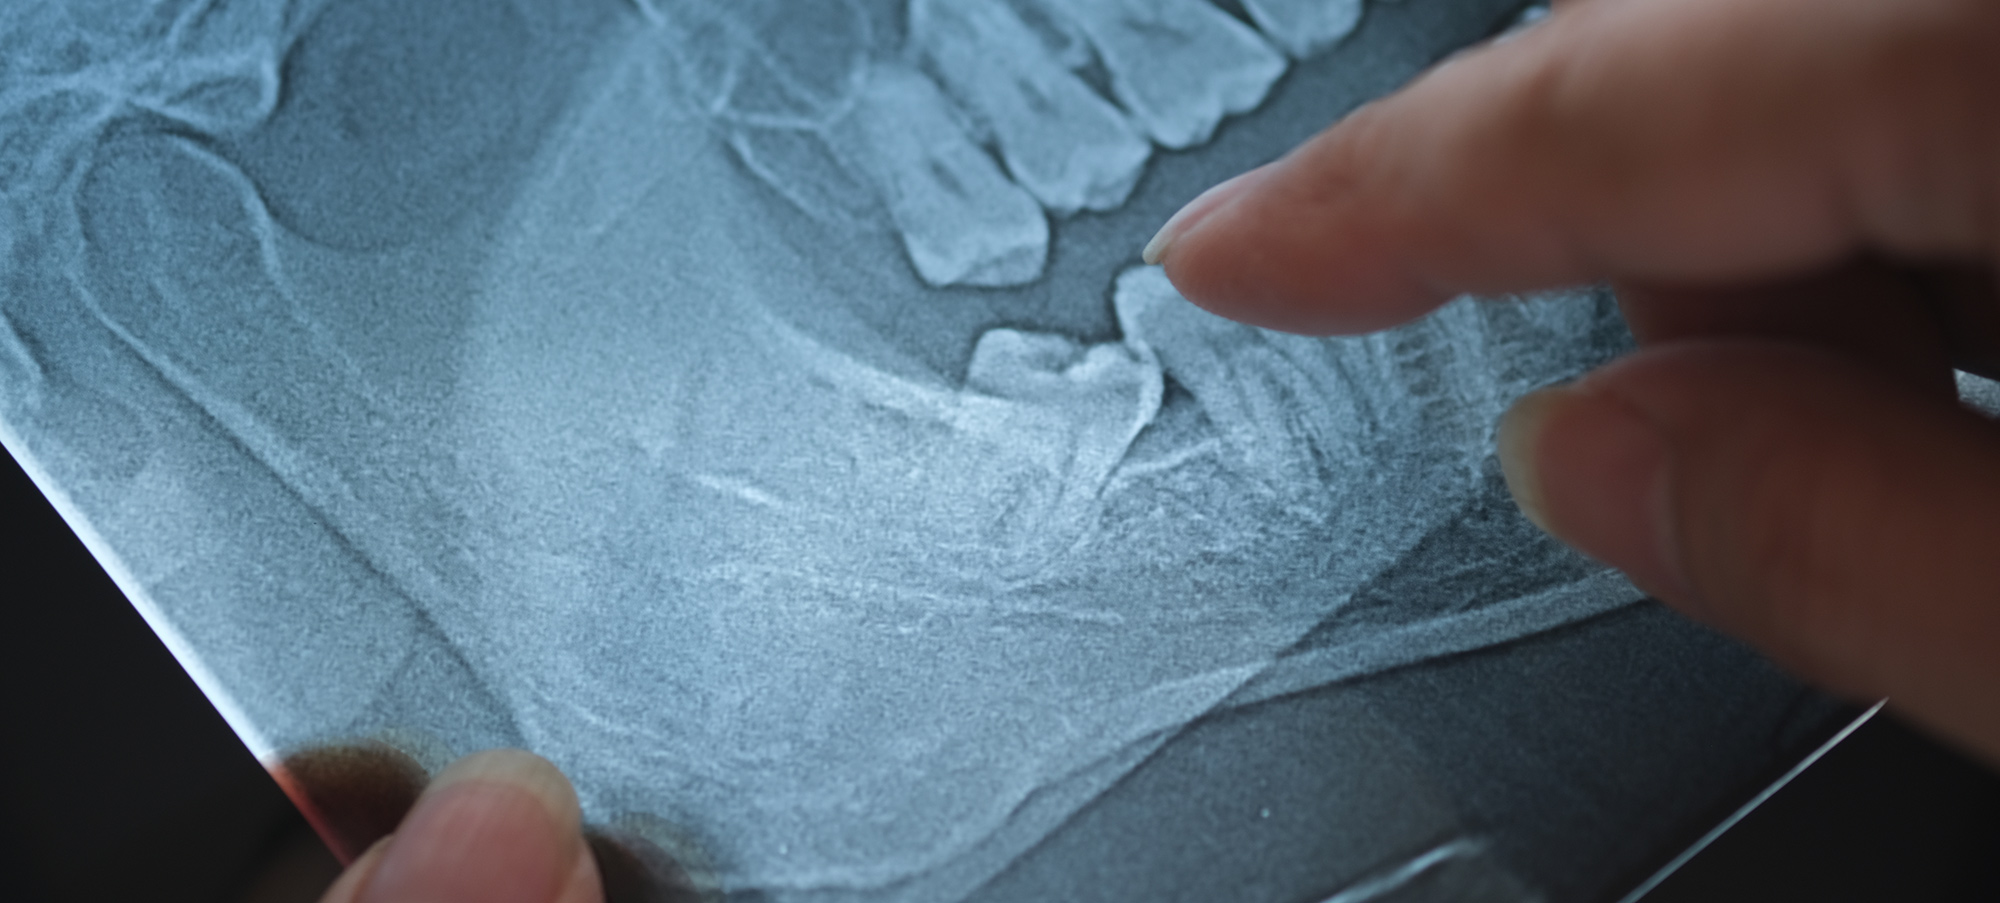

Your care begins with a consultation, where a full medical and dental history is taken. Imaging ( such as X-rays) is arranged to assess the position of the wisdom teeth and their relationship to nearby structures. The consultation also provides time to explain the procedure, anaesthetic options and any potential risks.